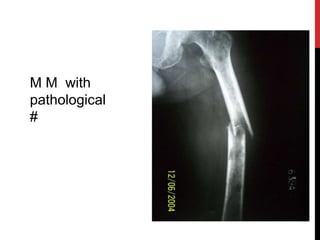

M M with

pathological

#

Multiple punched out lesions in skull & other flat bones.

Pathological wedge collapse of vertebra, commonly thoracic

spine. Pedicles usually spared.

Diffuse severe rarefaction of bones.